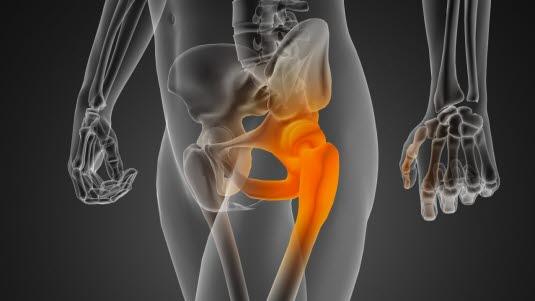

Bekkenet med hofteleddHofteleddet er et kuleledd som består av leddkule (lårbeinshodet) og leddskål (acetabulum). Leddflatene til lårbeinshodet og acetabulum er kledd med leddbrusk. Hofteleddet har en betydelig bevegelighet i alle plan og stabiliseres av leddkapselen, omgivende muskler, bruskskålen som kler den benede leddskålen og en bruskkant (labrum) som forlenger bruskskålen og stikker noen millimeter ut over den beinede kanten av hofteskålen. Labrum gjør dermed leddskålen dypere, gjør leddet stødigere og beskytter leddet.

Bruskskade oppstår i grenseflaten mellom lårbeinshodet og kanten på bruskskålen. Det skilles mellom to hovedtyper skader: Skader på labrumbrusken og skader eller forandringer på lårbeinshodet. Slike bruskskader fører til at små fliker av brusk stikker ut og kan komme i klem - derav navnet impingement eller innklemming.